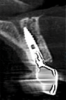

Fig 2. Immediate view of the implant and frictional abutment installed on the day of surgery.

Figure 2

After planning, the dental team opted to place an implant immediately after extracting the fractured left central incisor. Implant osteotomies were prepared according to manufacturer recommendation. A Morse-tapered 3.3 mm x 13 mm frictional implant was installed. A high primary stability of 40 Ncm was obtained, and immediate provisionalization of the implant was performed over a 2.5 mm x 3 mm x 6 mm frictional abutment for cemented restorations (Figure 2). An interim crown was then fabricated and cemented with a temporary cement.